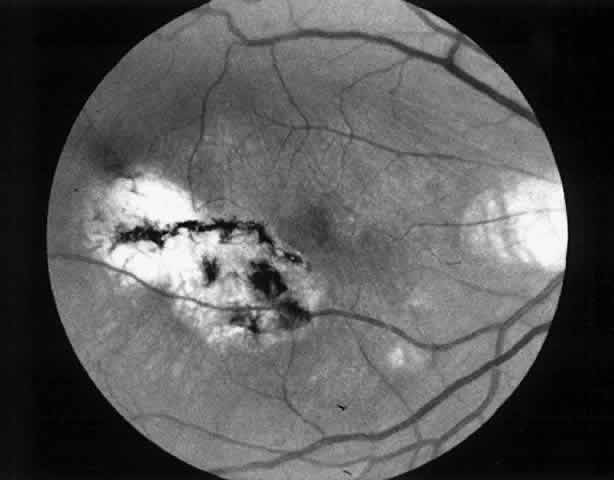

1. A 35-year-old patient with serpiginous choroidopathy developed a recurrent choroidal neovascular membrane extending into the fovea with a decrease in vision to 20/200 (6/60) (Fig. 7). Five months after surgery his visual acuity had improved to 20/25 (6/7.5) (Fig. 8).

Fig. 7. Preoperative fundus photograph of a 35-year-old patient with serpiginous choroidopathy and a recurrent subfoveal neovascular membrane (case 1). Visual acuity is 20/200 (6/60).